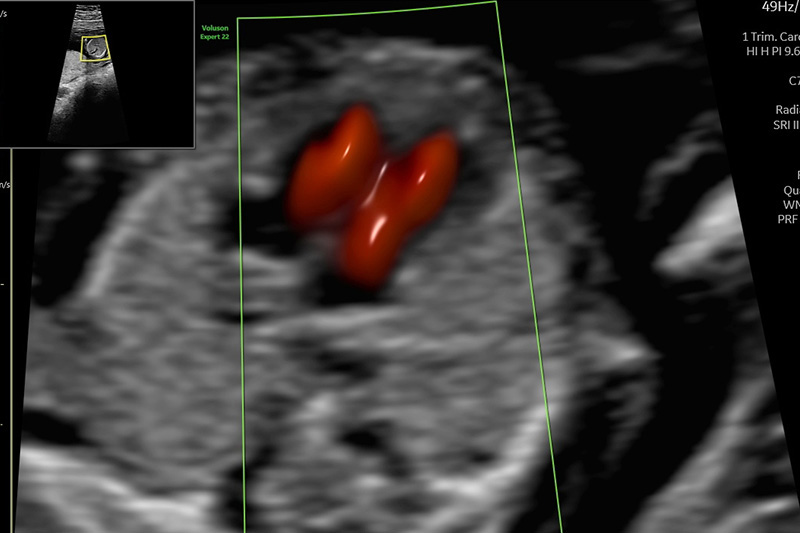

Bei der Untersuchung erfolgt eine Überprüfung des Entwicklungszustandes des Embryos und eine erste Organuntersuchung, soweit es die Verhältnisse des frühen Schwangerschaftsalters zulassen. Zahlreiche Fehlbildungen sind zu diesem Zeitpunkt bereits erkennbar, jedoch sind einige Organe (z.B. Herz, Wirbelsäule) zu diesem Zeitpunkt noch nicht abschließend beurteilbar. Eine abschließende Organbeurteilung kann erst zu einem späteren Zeitpunkt, üblicherweise in der ca. 20./22.SSW, beispielsweise über den weiterführenden Organultraschall (Feindiagnostik) erfolgen.